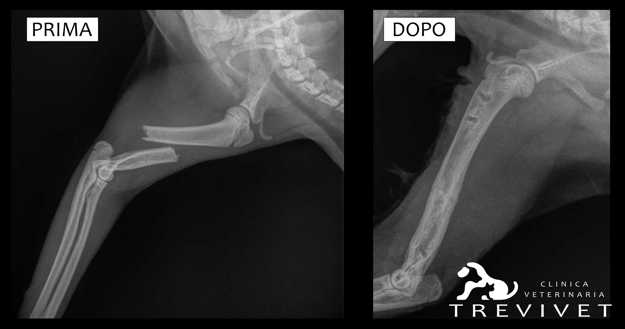

All’esame radiografico in sedazione si evince la presenza di una frattura trasversa dell’omero del 2° terzo medio con contrazione e dislocazione mediale del moncone distale.

In accordo coi proprietari si decide di effettuare una riduzione chirurgica della frattura, con stabilizzazione del segmento osseo attraverso l’utilizzo di un fissatore esterno TIE-IN mono-planare bi-laterale (tipo IIA) formato da chiodi di Kirshner filettati, collegati a un barra in acciaio con morsetti Mainard e viene aggiunta una barra antirotazionale.

La ripresa di Favy è stata piena e soddisfacente sia dal punto di vista clinico-ortopedico che di qualità di vita.